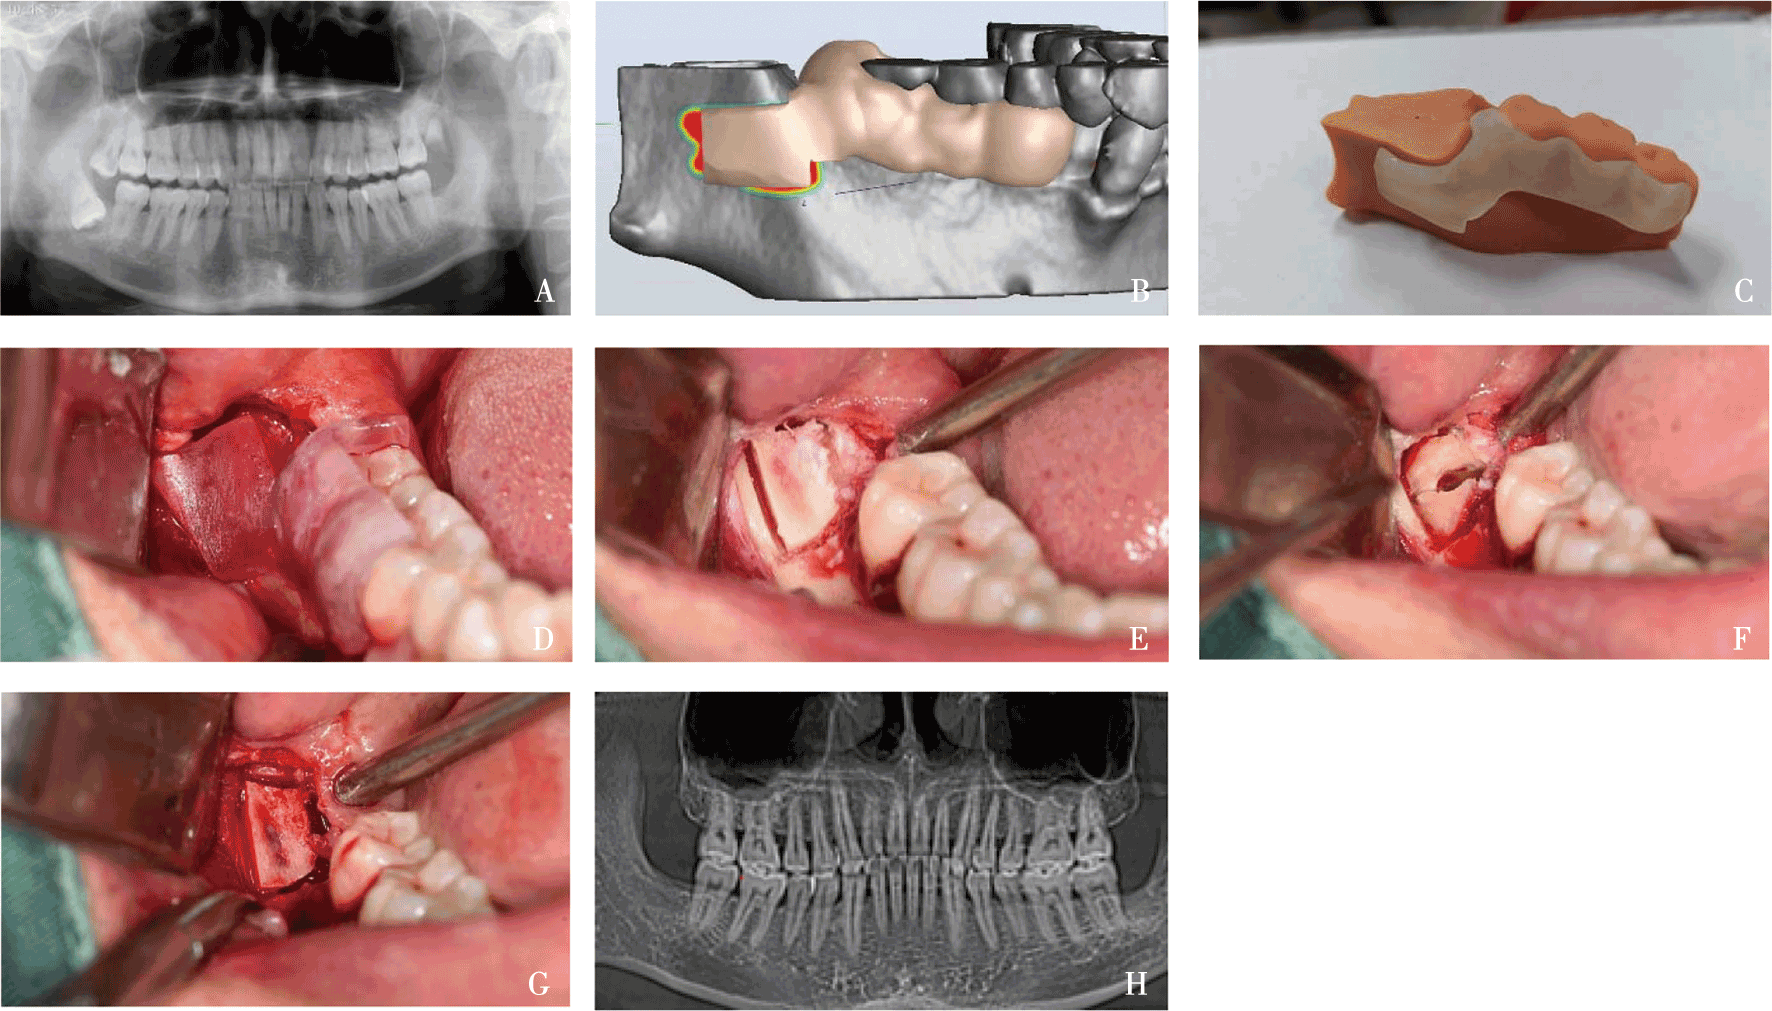

Tang XP, Lai QG, Xue RQ, et al. Hard tissue preservation and recovery in minimally invasive alveolar surgery using three-dimensional printing guide plate[J]. 2022, 33(5): e476-e481.

Yan ZY, Xu JY, Zhang JY, et al. Optimal tooth sectioning using a surgical handpiece and elevator: A finite element study of horizontally deeply impacted mandibular third molars[J]. Clin Oral Investig, 2024, 28(8): 439.